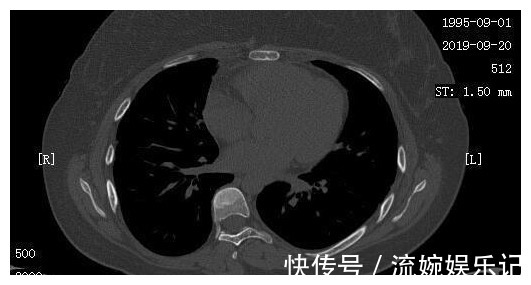

我院肿瘤科医生根据小周的一般情况,也马上下了病危,提醒小周家属,随时可能出现去世的可能。在小周父母很伤心的时候,反而是小周心态积极,安慰父母:我们就积极治疗吧,能够到哪一天就到哪一天吧。同时,根据小周的病情状况,肿瘤科医生也马上制定了治疗方案,给予了小周化疗以及靶向治疗,通过调整靶向药物,小周从2018年9月23日开始口服某靶向药物治疗。经过治疗,小周的一般情况居然逐渐好转起来,同时也顺利出院回家进行调养,到2019年4月12日,小周又再次在我院复查了CT,我们惊喜地发现,她双肺的病灶明显减少,甚至几乎看不到了。

小周和她的家人非常高兴,同时也更加积极的配合医生进行治疗,加上小周平时也按时、适量的锻炼,逐渐的,小周发现自己的食欲也好起来了,抵抗力也增强了,到9月份再次复查的时候,我们发现小周的肺部情况非常好,同时全身骨转移灶也减少了。